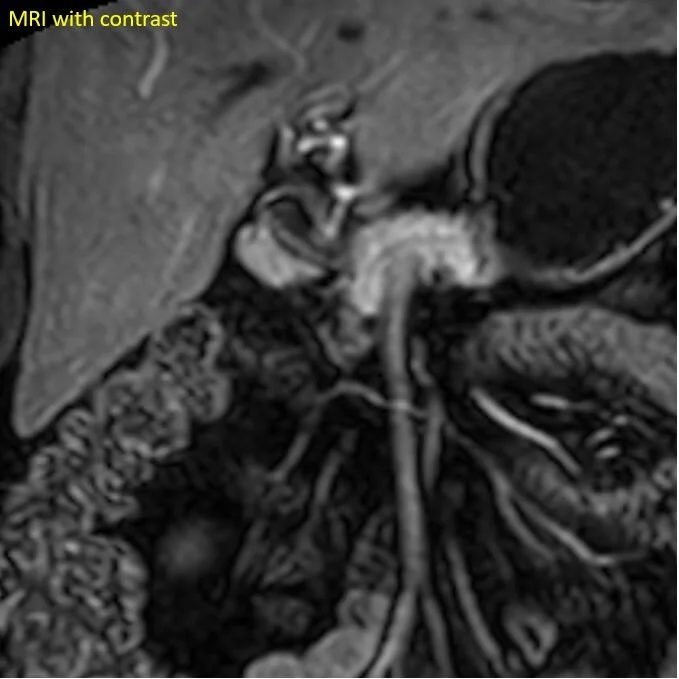

So yes, the pancreas is normal, but there is a small accessory pancreas adjacent to the pylorus/duodenal bulb. This was hiding in plain sight on multiple prior exams, and is nicely seen in retrospect on a previous MRI.

Previous MRI shows the heterotopic pancreas nicely. It was hiding in plain sight!